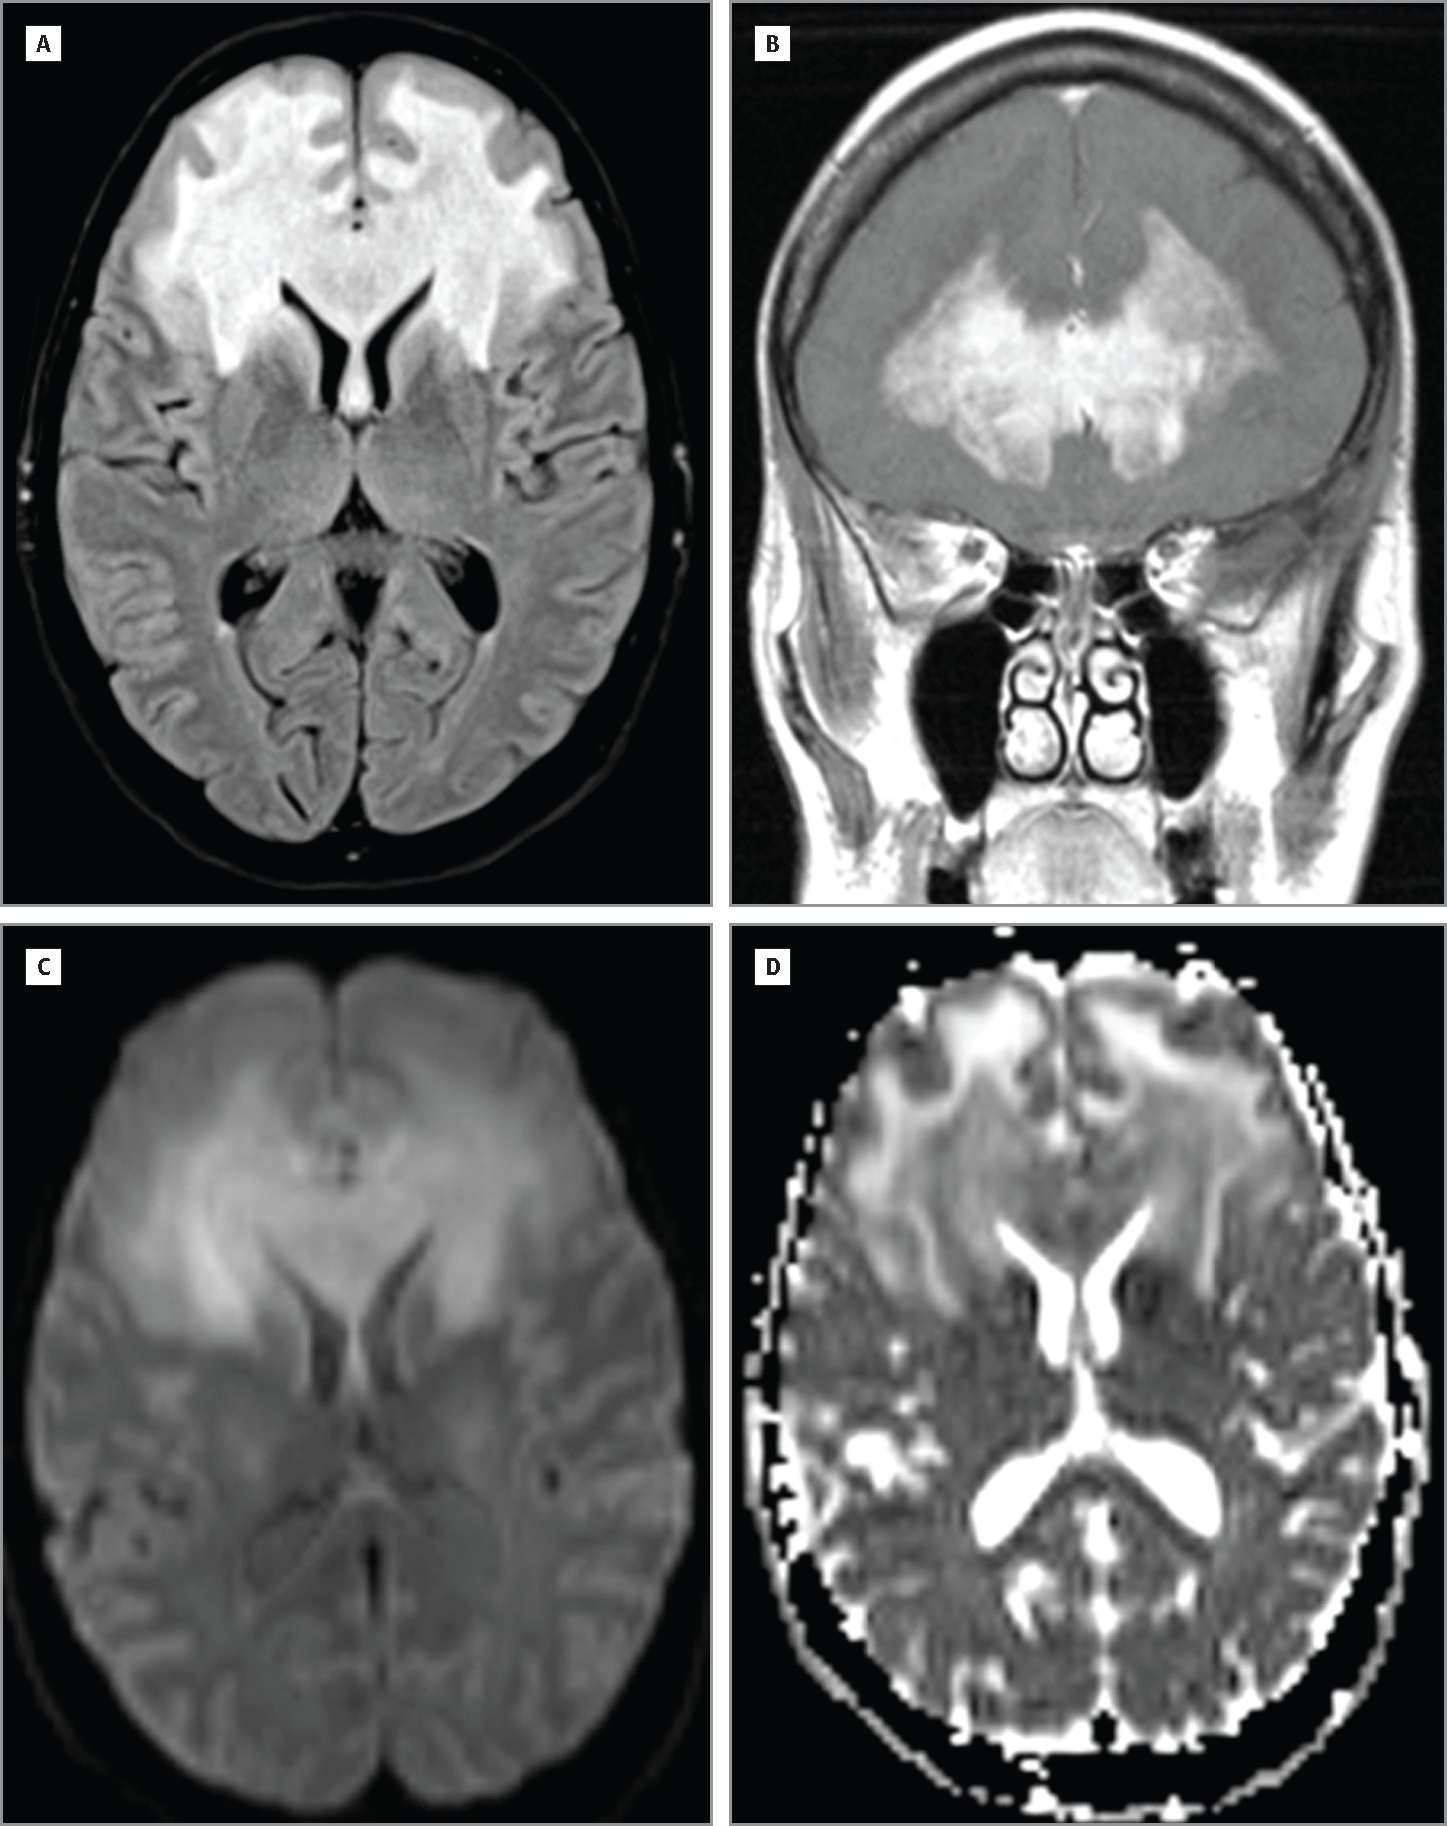

头颅MRI提示双侧额叶和胼胝体前部对称性强化病灶,DWI弥散受限。

(A:FLAIR;B:T1增强;C:DWI;D:ADC)

讨论对本例患者头颅MRI的细致分析有助于临床诊断。病灶异乎寻常的对称性,可提示代谢性或中毒性脑病,脑白质营养不良或肿瘤。有一些值得注意的特征,提示淋巴瘤的可能,从而可指导进一步的评估和处理。①侧脑室旁轻微的占位效应和胼胝体的增大提示病灶是一肿块;②病灶均匀强化形式符合免疫健全的中枢神经系统淋巴瘤患者;③位于脑室旁的病灶并非脑淋巴瘤特有,但却比较常见,同样的,胼胝体受累也是如此;④弥散受限在脑淋巴瘤中比较普遍。充分认识疾病特征性的影像学改变有助于初步诊断的形成与随后检查的选择,对患者和医生而言大有裨益。